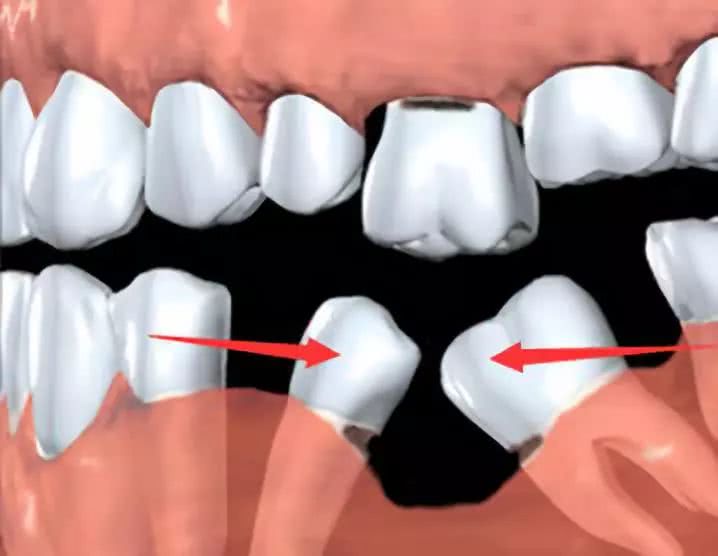

牙齿承受的咀嚼力是有一定限度的,当个别牙齿缺失后,咀嚼力集中在余留牙上,由于咀嚼力超过了余留牙的承受限度,致使余留牙齿造成创伤而产生牙周膜水肿、牙龈萎缩、牙槽骨吸收、牙齿松动等牙周疾患。

(缺牙的危害不容小觑)